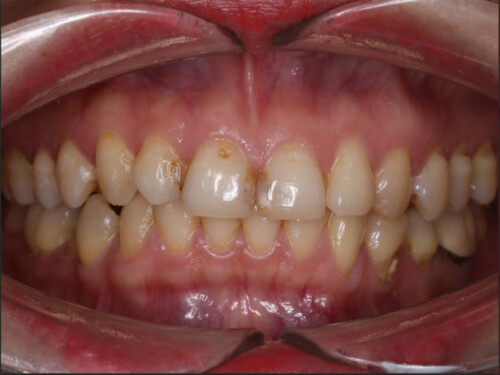

Hình 1: Bệnh nhân phụ nữ mang thai thường gặp nhiều vấn đề về sức khỏe răng miệng.

Trong thời gian mang thai, phụ nữ thường trải qua nhiều biến đổi về sức khỏe răng miệng do sự thay đổi hormone trong cơ thể. Theo Hiệp hội Nha sĩ Mỹ, khoảng 40% phụ nữ mang thai gặp phải các vấn đề như sâu răng, nhiễm trùng lợi, viêm lợi và viêm nha chu. Những vấn đề này có thể ảnh hưởng đến sức khỏe của thai nhi và tăng nguy cơ mắc các bệnh lý răng miệng trong tương lai. Chế độ ăn uống không lành mạnh và thói quen vệ sinh răng miệng không đúng cách có thể dẫn đến những vấn đề nghiêm trọng cho cả mẹ và bé. Vì vậy, chăm sóc răng miệng trong thời kỳ mang thai là rất cần thiết và cần được chú trọng.